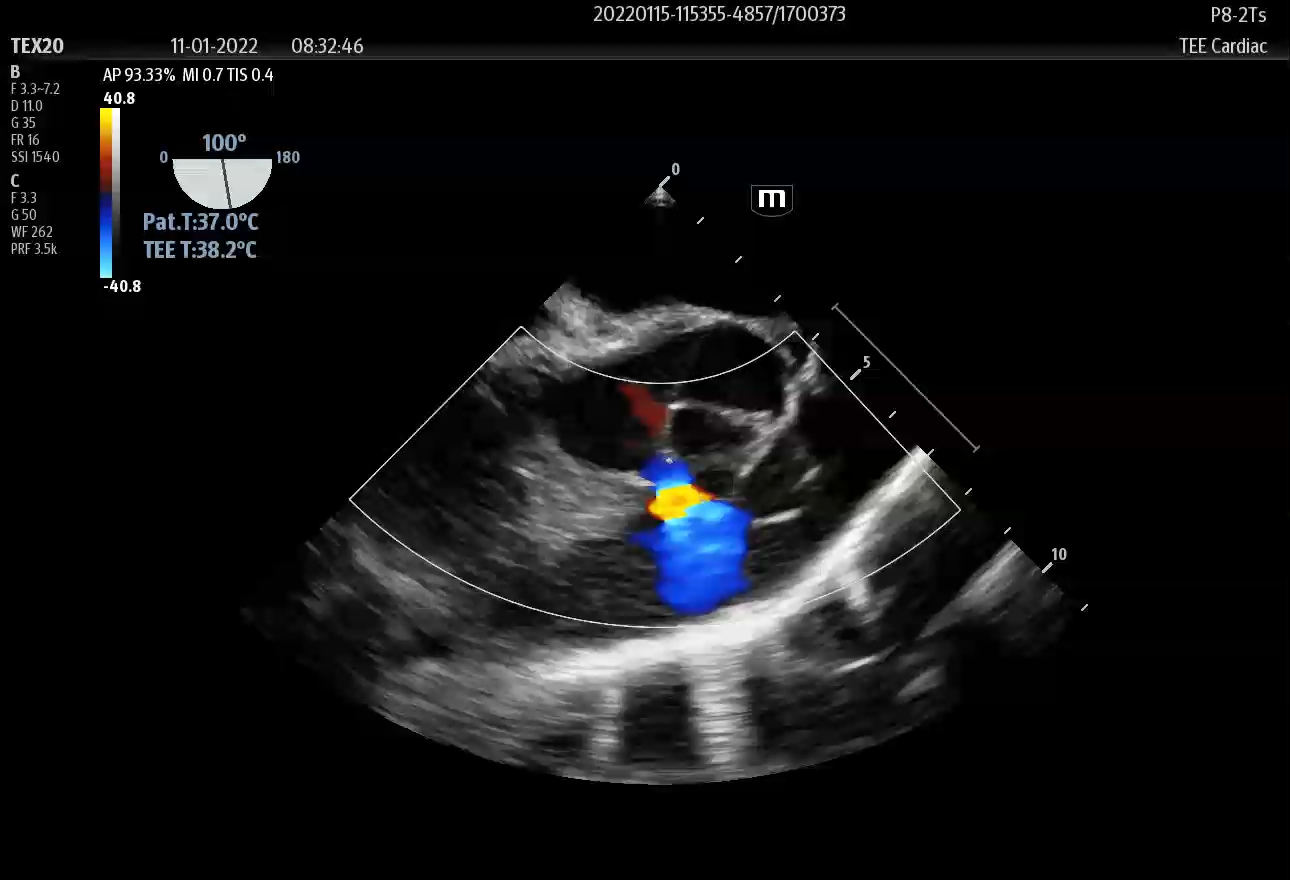

1、室间隔由膜部、漏斗部和肌部组成,根据缺损部位不同,可将室间隔缺损分为三型:

膜周型室间隔缺损:

2、为膜部缺损,是室间隔缺损中最常见的一型。

3、双动脉下型室间隔缺损:为漏斗部缺损,还可进一步分为干下型、嘴内型。

4、肌部型室间隔缺损:为肌部缺损。